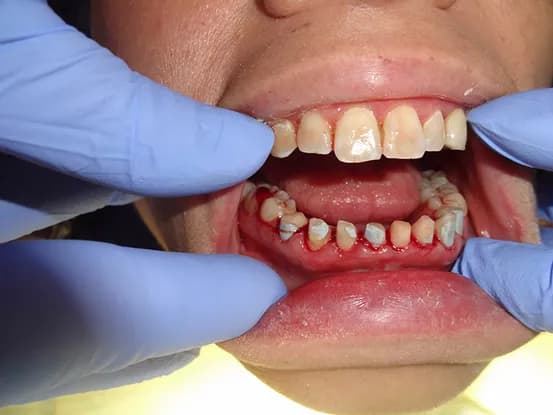

Case 7

38 year old female with extensive cervical caries from a high sugar diet and poor oral hygiene. 12 units of porcelain crowns and composite fillings to restore form and function followed by frequent recall visits